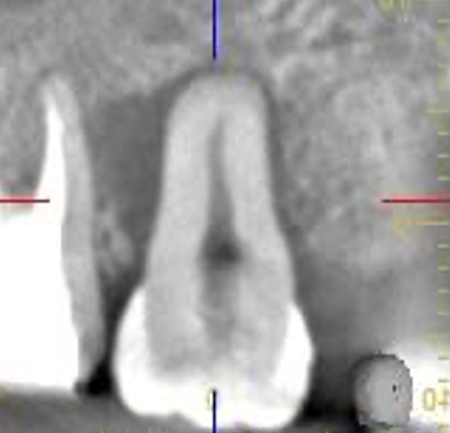

| STEP3 移植後レントゲン | STEP4 5ヶ月後レントゲン (歯槽硬線と歯根膜腔が認められる) |

![]() |